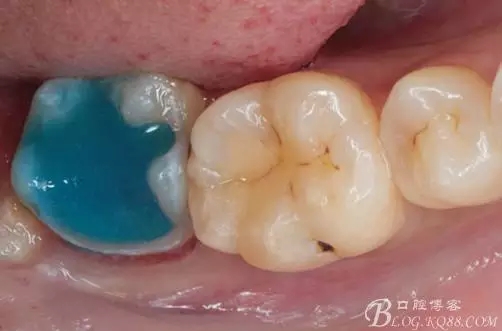

一周后復(fù)診,37臨時(shí)充填物完好。去除臨時(shí)充填物,清潔基牙,試戴嵌體,就位良好,邊緣密合。取下嵌體,常規(guī)處理,9.5%HF處理20S,沖洗一分鐘,95%酒精蕩洗5分鐘?;劳磕?7%的磷酸凝膠,釉質(zhì)區(qū)域酸蝕30S,本質(zhì)區(qū)域15S。粘固用的是3M第八代粘接劑套裝,照說明書逐步操作。最終固化時(shí)涂滿阻氧劑,每個(gè)牙面最少光照30S,光固化燈用漸強(qiáng)模式。常規(guī)調(diào)合,配合硅膠尖套裝拋光。術(shù)后常規(guī)醫(yī)囑,不適隨診。

④嵌體顏色與基牙的差異也是一遺憾。